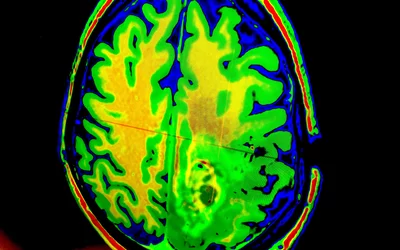

Neuroradiology